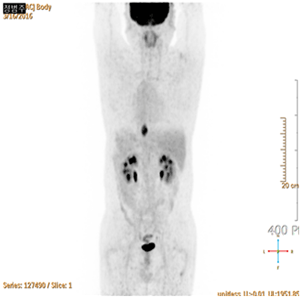

식도암 환자의 PET-CT